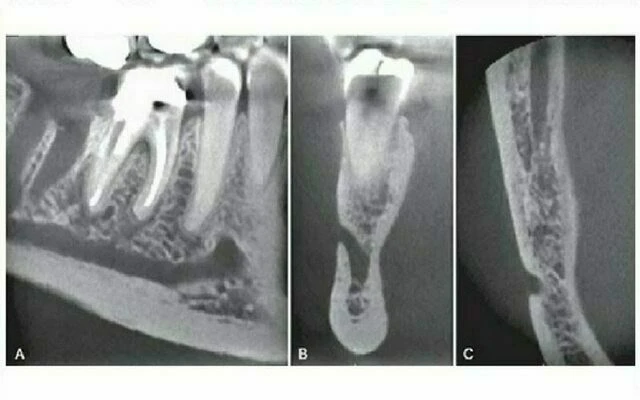

Hình ảnh X quang của ống hàm dưới là một đường đen với đường biên giới phía trên và dưới cản quang do được tạo nên bởi các phiến xương mỏng bao quanh ống. Đôi khi biên giới chỉ thấy một phần hoặc thấy toàn bộ. Độ rộng của ống khác nhau giữa các bệnh nhân nhưng thường giống nhau ở phần phía trước đến vùng răng cối lớn thứ ba. Đường đi của ống giữa lỗ hàm dưới và lỗ cằm khá rõ. Chỉ có là hiếm khi hình ảnh liên tục phía trước hướng về phía đường giữa có thể thấy rõ trên X quang.

Mối quan hệ giữa ống thần kinh răng dưới với các chân răng dưới có thể khác nhau, có thể tiếp xúc gần với các chân răng cối và chân răng cối nhỏ thứ hai đến việc không có liên quan gì đến các răng sau. Tuy nhiên, ở hình ảnh bình thường thì ống hàm dưới tiếp xúc với chóp răng cối lớn thứ ba, và khoảng cách giữa nó với các chân răng tăng lên khi nó chạy về phía trước. Khi chóp các răng cối có hình chụp chồng lên ống này thì lamina dura có thể bị chiếu tia nhiều, tạo ấn tượng rằng thiếu lamina dura hoặc khoảng dây chẳng nha chu dày lên, tức thấu quang hơn so với mức độ bình thường của bệnh nhân. Để chắc chắn về sự toàn vẹn của răng, cần thực hiện các thử nghiệm lâm sàng khác (chẳng hạn thử độ sống tủy). Vì ống này thường nằm ngay dưới chóp các chân răng sau, thay đổi góc chụp theo chiều dọc ở một phim thứ hai sẽ không giúp tách được hình ảnh của ống và chóp răng.

Nghiên cứu mô học cho thấy rằng thần kinh xương ổ răng dưới thường dạy xuyên qua xương hàm dưới như một thân cây lớn với các nhanh mở rộng về phía chóp răng. Tuy nhiên, có nhiều nhánh nhỏ hơn của thần kinh xương ổ răng dưới chạy song song với thân thần kinh chính. Ống chẻ đôi dạng này thấy được phổ biến nhất trên phim panorex và cone-beam. Bệnh nhân có ống chẻ đôi có nguy cơ gây tê không hiệu quả cao hơn và khó khăn trong việc phẫu thuật ở xương hàm, bao gồm khi cắm implant hoặc do chấn thương.